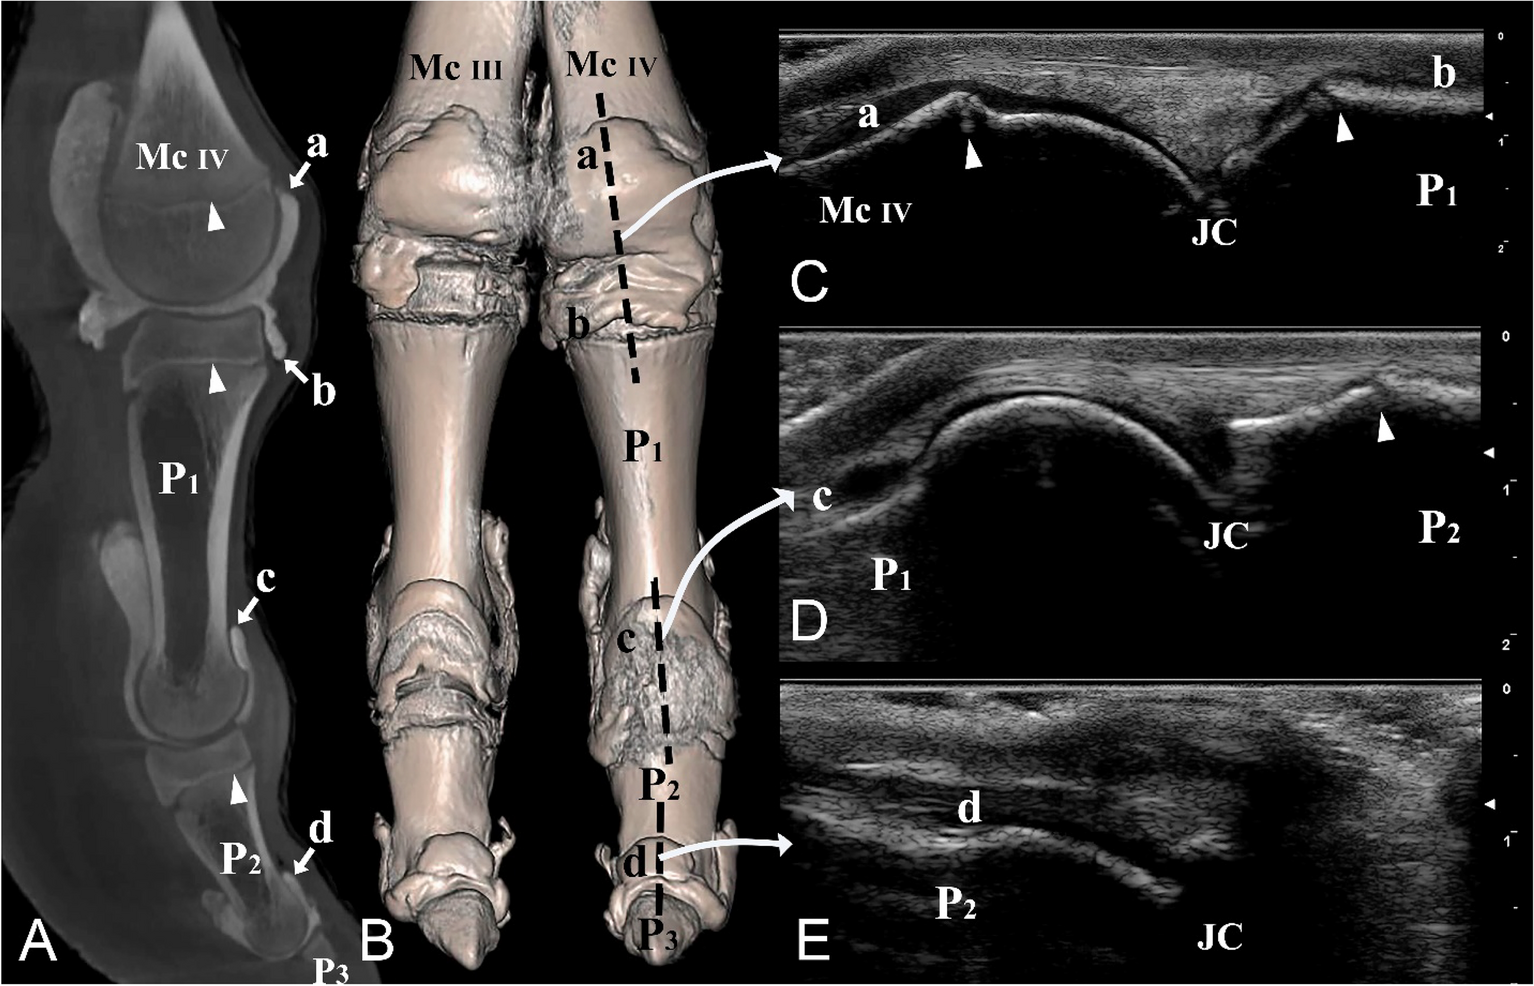

Figure 5

From: Arthrocentesis approaches to the phalangeal joints of the one humped camel (Camelus dromedarius)

Dorsal and lateral views of the left distal forelimb and digit IV. (A) Sagittal plane CT image; (B) three-dimensional reconstruction (the black dotted line indicating the dorsal placement of the ultrasound probe), (C) longitudinal dorsal ultrasound image of the metacarpophalangeal joint, (D) longitudinal dorsal ultrasound image of the proximal interphalangeal joint, and (E) longitudinal dorsal ultrasound image of the distal interphalangeal joint. Mc III distal end of metacarpal bone III, Mc IV distal end of metacarpal bone IV, P1 proximal phalanx, P2 middle phalanx, P3 distal phalanx, a proximal dorsal recess of the metacarpophalangeal joint, b distal dorsal recess of the metacarpophalangeal joint, c proximal dorsal recess of the proximal interphalangeal joint, d proximal dorsal recess of the distal interphalangeal joint, JC joint cavity. White arrowheads indicate the epiphyseal lines.